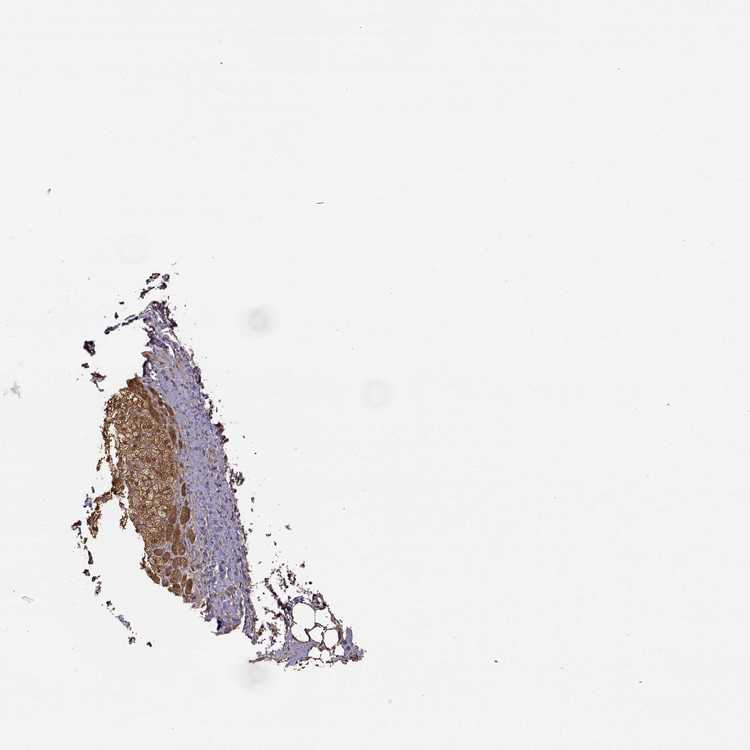

ADRENAL GLAND - Antibody stainingi

Antibody staining in the annotated cell types in the current human tissue is reported as not detected, low, medium, or high, based on conventional immunohistochemistry profiling in selected tissues. This score is based on the combination of the staining intensity and fraction of stained cells.

Each image is clickable and will lead to virtual microscopy that enables deeper exploration of all samples and also displays staining intensity scores, fraction scores and subcellular localization as well as patient and tissue information for each sample.

Antibody HPA000556

Glandular cells Medium